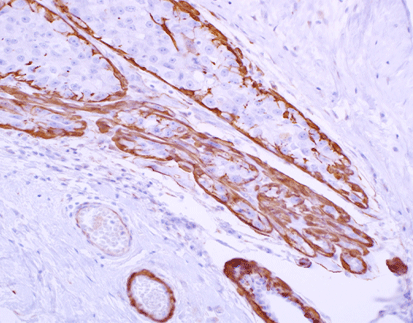

Mesothelioma tissue stained with Calretinin/CR

CR is an intracellular calcium-binding protein that belongs to the troponin c-superfamily.It is mainly used for the diagnosis of mesothelioma, especially epithelial mesothelioma, with sensitivity up to 100% and specificity up to 50%, and also for the study of neurological diseases.